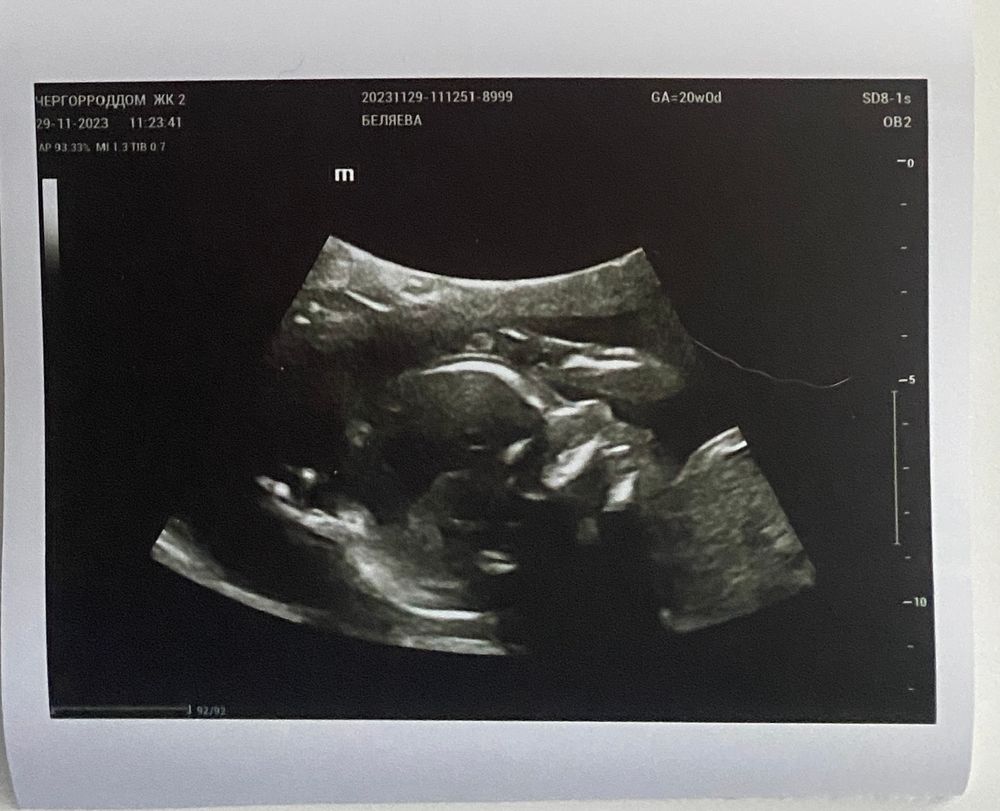

Что произошло за время, пока в дневник не писала?

Встретила 30 недель, вышла в декретный отпуск. Тогда же сделали первый КТГ - плохой (монотонный). А на следующий день второй КТГ - хороший (распихала ребёнка тычками вбок и белевской пастилой)😂